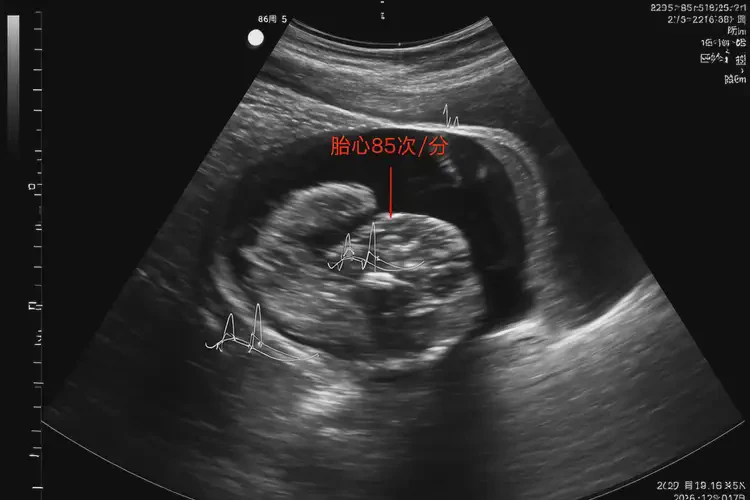

孕16周5天胎心率85有危險(xiǎn)嗎

胎心率85次/分鐘在孕16周5天時(shí)可能存在風(fēng)險(xiǎn)

胎心率是評(píng)估胎兒健康狀況的重要指標(biāo)之一。在孕16周5天時(shí),正常胎心率范圍通常在140-170次/分鐘之間。胎心率低于120次/分鐘或高于180次/分鐘可能提示異常情況。胎心率85次/分鐘明顯低于正常范圍,可能存在一定的風(fēng)險(xiǎn),需要引起重視。

孕16周5天胎心率85有危險(xiǎn)嗎(圖1)